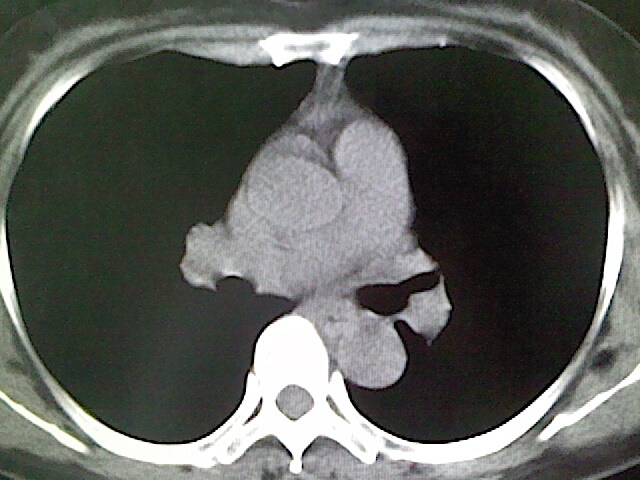

女,52岁,咳嗽,咳痰多日

左下肺陈旧纤维索条!

左肺舌段炎性改变

我见过几例,为炎症后纤维条索

慢性炎症后改变

考虑慢性炎性病灶粘连牵拉改变。

左肺舌叶纤维锁条病变。

左肺上叶下舌段炎症并局部胸膜反应。

左肺舌叶纤维索条影。

左肺舌叶段陈旧性病变

左肺舌段炎性反应。片子的质量太不好了。

左肺舌段炎性

炎性改变

左肺舌叶纤维索条影